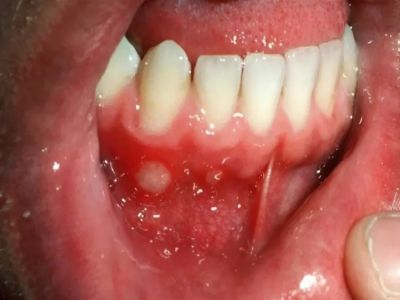

牙龈

小水疱

创伤性溃疡患者牙龈上出现一个小疱图

创伤性溃疡牙龈上有一个白色、圆形的小疱,患者自觉疼痛明显,小疱的表面黏膜破溃后漏出红色糜烂面,水疱的基底边缘有炎性浸润。